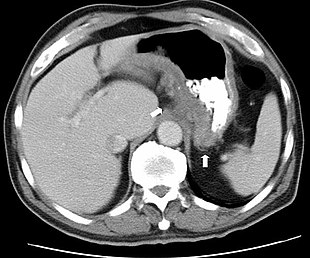

Bei den bildgebenden Verfahren der Radiologie – insbesondere den anhand der Untersuchungsdaten errechneten Darstellungen von Körperquerschnitten bestimmter Schichtdicke (Tomographie) – spielen Transversalschnitte eine wichtige Rolle. Sie stellen die aufgenommenen Bilddaten in verschiedenen Transversalebenen dar, die mit bestimmten Abständen längs der Körperachse aufeinander folgen und so in axialer Schichtung ein Bild des Körpers geben. Bei der tomographischen Untersuchung wird eine Serie transaxialer Schnittbilder erstellt, die den untersuchten Körper Schicht für Schicht transversal darstellen.